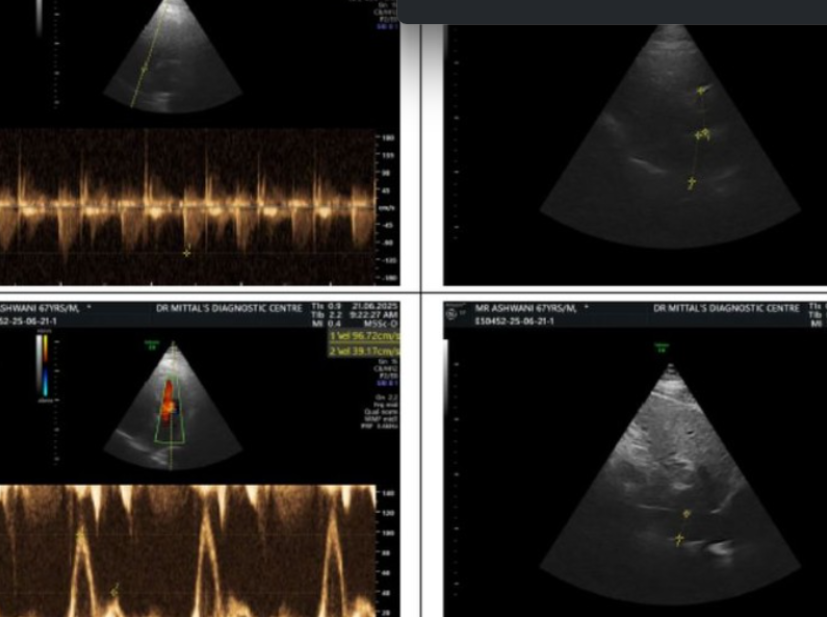

ECHO IN ROHINI